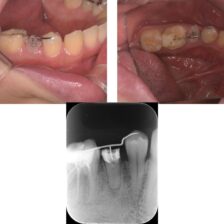

精密根管治療により、

歯を残せる可能性を最大限に

当院ではCT・マイクロスコープ・セファロなどの精密検査機器を活用し、歯を残すための選択肢をできる限りご提案します。

歯髄温存治療(MTA)や歯冠長延長術、矯正的挺出など、専門的な治療にも対応。

また、痛みに配慮した麻酔方法で、安心して治療を受けていただけます。